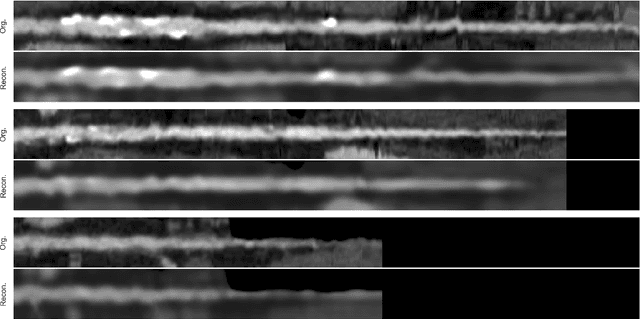

Abstract:Diffusion magnetic resonance imaging is a noninvasive imaging technique which can indirectly infer the microstructure of tissues and provide metrics which are subject to normal variability across subjects. Potentially abnormal values or features may yield essential information to support analysis of controls and patients cohorts, but subtle confounds affecting diffusion MRI, such as those due to difference in scanning protocols or hardware, can lead to systematic errors which could be mistaken for purely biologically driven variations amongst subjects. In this work, we propose a new harmonization algorithm based on adaptive dictionary learning to mitigate the unwanted variability caused by different scanner hardware while preserving the natural biological variability present in the data. Overcomplete dictionaries, which are learned automatically from the data and do not require paired samples, are then used to reconstruct the data from a different scanner, removing variability present in the source scanner in the process. We use the publicly available database from an international challenge to evaluate the method, which was acquired on three different scanners and with two different protocols, and propose a new mapping towards a scanner-agnostic space. Results show that the effect size of the four studied diffusion metrics is preserved while removing variability attributable to the scanner. Experiments with alterations using a free water compartment, which is not simulated in the training data, shows that the effect size induced by the alterations is also preserved after harmonization. The algorithm is freely available and could help multicenter studies in pooling their data, while removing scanner specific confounds, and increase statistical power in the process.